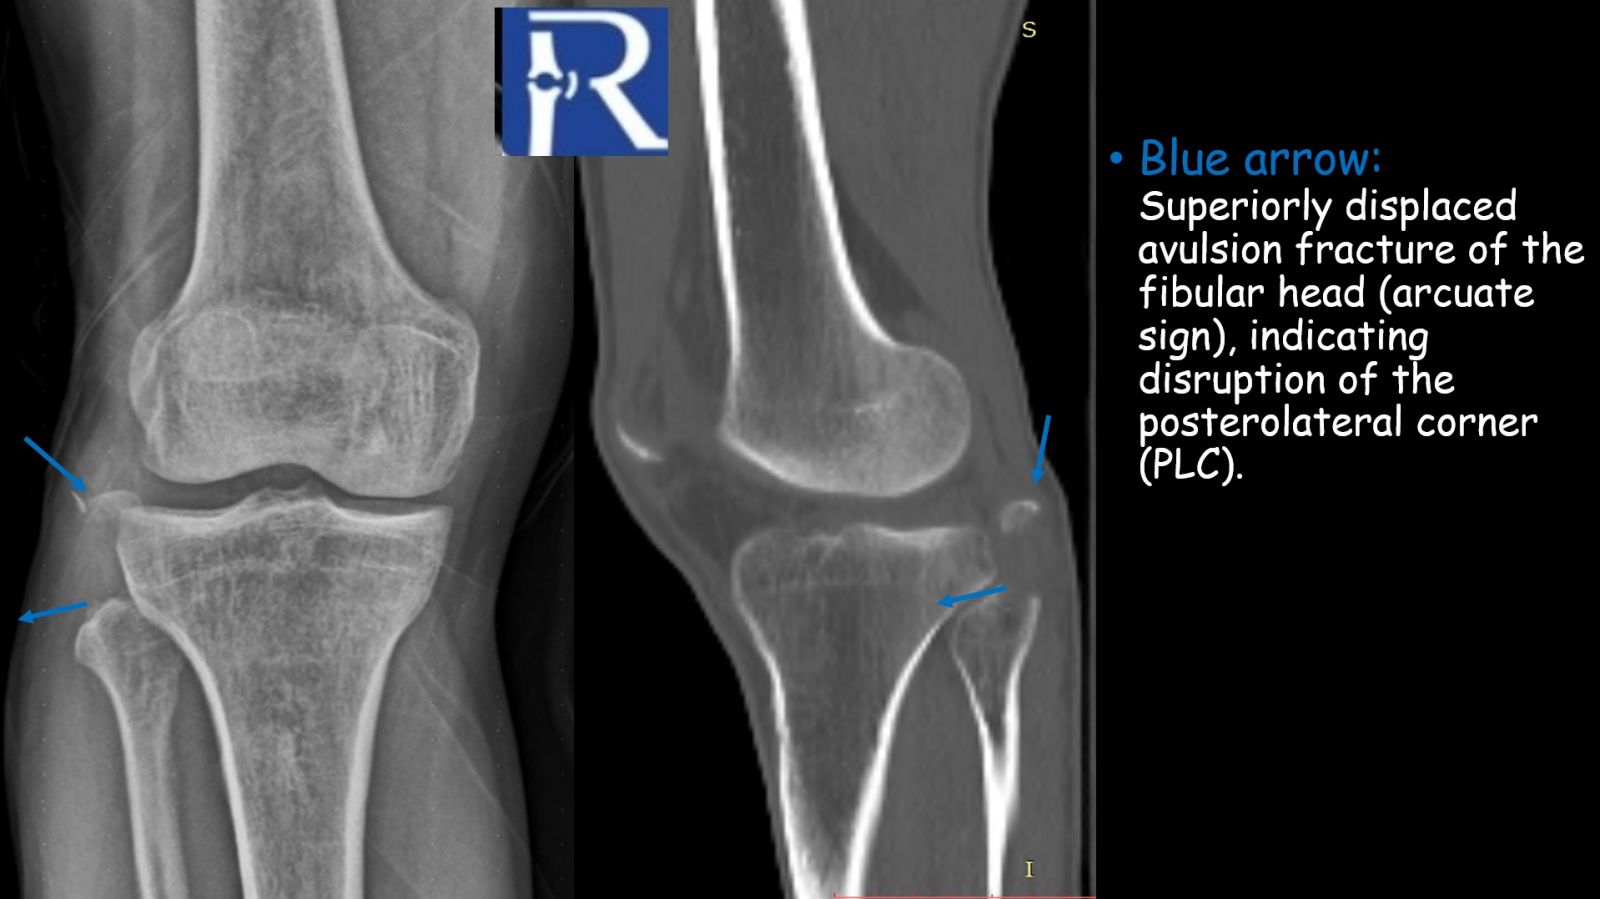

Radiographic findings:

Plain radiographs demonstrated a superiorly displaced avulsion fracture of the fibular head, consistent with the arcuate sign. Although often subtle, this finding represents an avulsion at the insertion site of the arcuate ligament complex and is a well-recognized radiographic marker of posterolateral corner (PLC) injury. The fracture fragment is typically attached to the fibular (lateral) collateral ligament, the biceps femoris tendon, or both, and its size and displacement pattern may vary depending on the injured structure.

.jpeg)